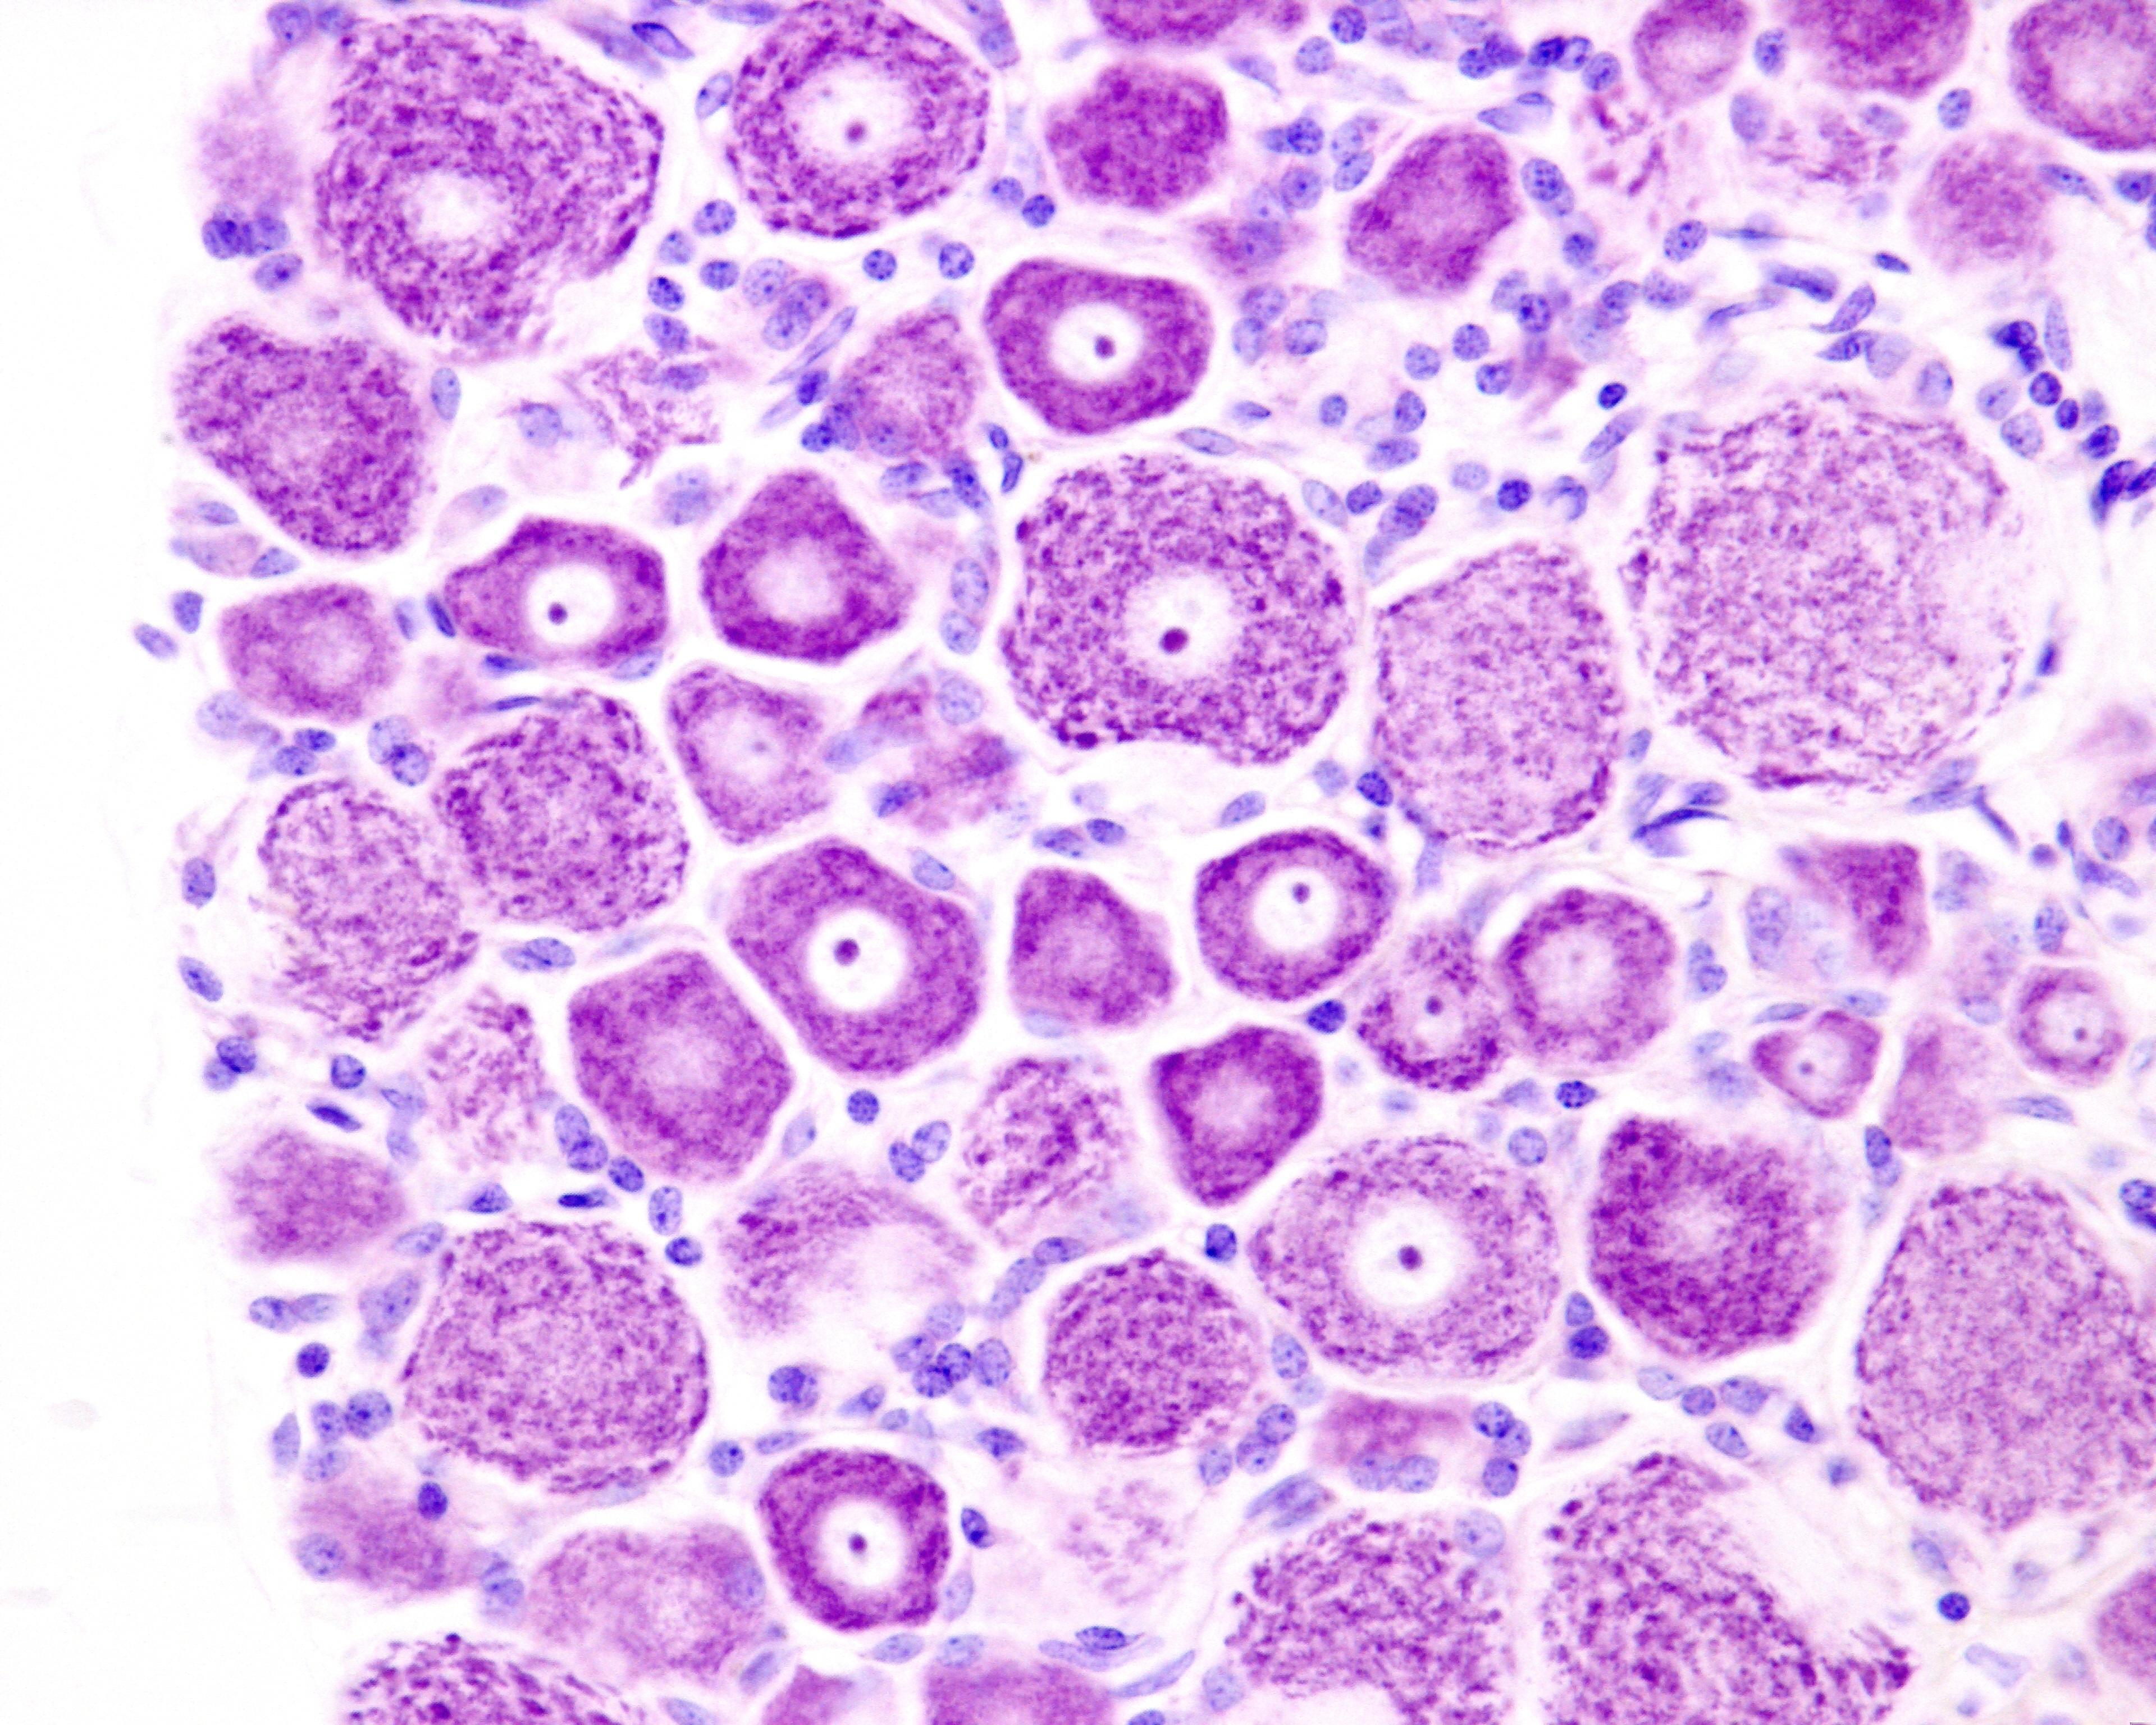

Tıbbi bilim dünyasında önemli bir gelişme yaşanmıştır. Kan kanserinin bir türü olan lösemiyi tedavi etmek amacıyla kök hücre nakli yapılan bir hasta, yedi yıl üç ay boyunca HIV virüsünün hiçbir belirtisini göstermemiştir. Bu durum, hastanın resmi olarak HIV'den iyileşmiş sayılmasını sağlamış ve kendisini, bu başarıyı elde eden yedinci kişi konumuna getirmiştir. Ancak bu vaka, önceki altı hastanın hikayesinden çok daha önemli bir farkı içermektedir: söz konusu hasta, virüse dirençli olmayan kök hücreler almıştır.

En son vaka, Cenevre hastasının gerçekten iyileştirildiği fikrini güçlendirmektedir. Ekim 2015'te, o sırada 51 yaşında olan bir erkek, lösemi tedavisi için kök hücre nakli almıştır. Hastanın HIV pozitif olması, tedavi sürecini daha karmaşık hale getirmiştir. Lösemiyi kontrol altına almak için kendisine yoğun kemoterapi uygulanmış, bu da bağışıklık hücrelerinin büyük çoğunluğunu yok etmiştir. Böylece donör kök hücrelerinin sağlıklı bir bağışıklık sistemi oluşturması için yer açılmıştır. İdeal olarak, hasta HIV'e dirençli kök hücreler alacaktı, ancak bu tür hücreler mevcut olmadığından, doktorlar CCR5 geninin bir normal ve bir mutasyona uğramış kopyasını taşıyan hücreleri kullanmışlardır. Tedavi sırasında, hasta antiretroviral terapi (ART) adı verilen standart HIV ilaçlarını almaya devam etmiştir. Bu ilaç kombinasyonu, virüsü tespit edilemez seviyelere indirerek, hem başka insanlara bulaşmasını engeller hem de donör hücrelerin enfekte olma riskini azaltır.